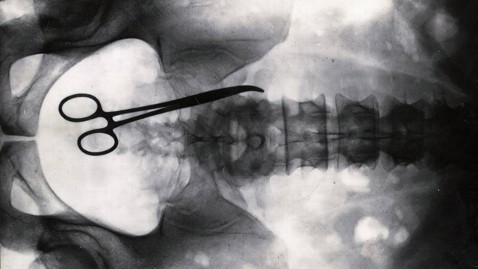

Medical malpractice occurs when a doctor, dentist, therapist, nurse, or other medical professional fails to competently perform his or her medical duties and as a result the patient is injured. Sadly, medical malpractice is a significant problem leaving thousands of patients injured or dead. In 2012 31% of medical malpractice victims died while 19% of the victims suffered significant, permanent injuries. Any medical mistake is terrifying as the results can be devastating. Some cases, however, are particularly shocking.